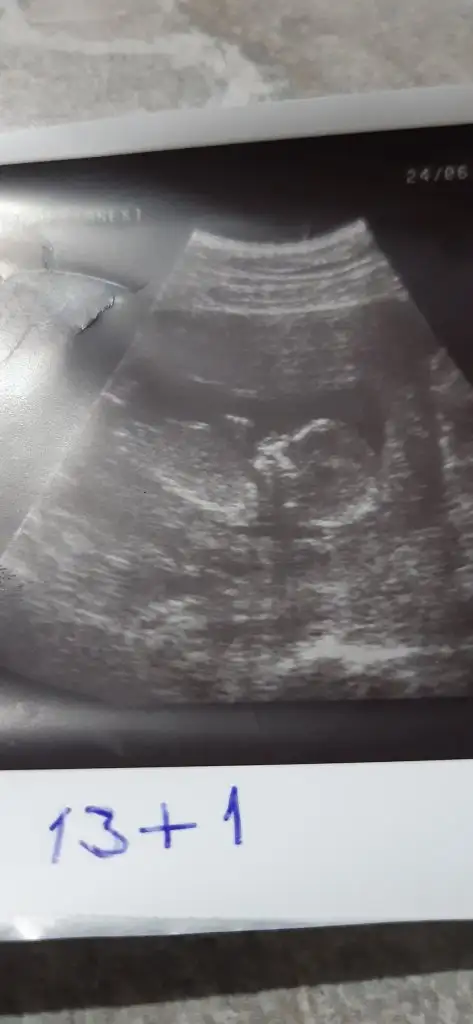

11 12 13 hafta olmalı cnmIkra meyra 15 haftalık bacakları kapalıydı. Erkeğe benzetti doktor. Sizdende bir tahmin alabilir miyim :)Eki Görüntüle 2655284

Net değil ama kız sanki paralel iniyor nubu kız gibi gibiMerhaba

hayirlisi insallah:)Net değil ama kız sanki paralel iniyor nubu kız gibi gibi